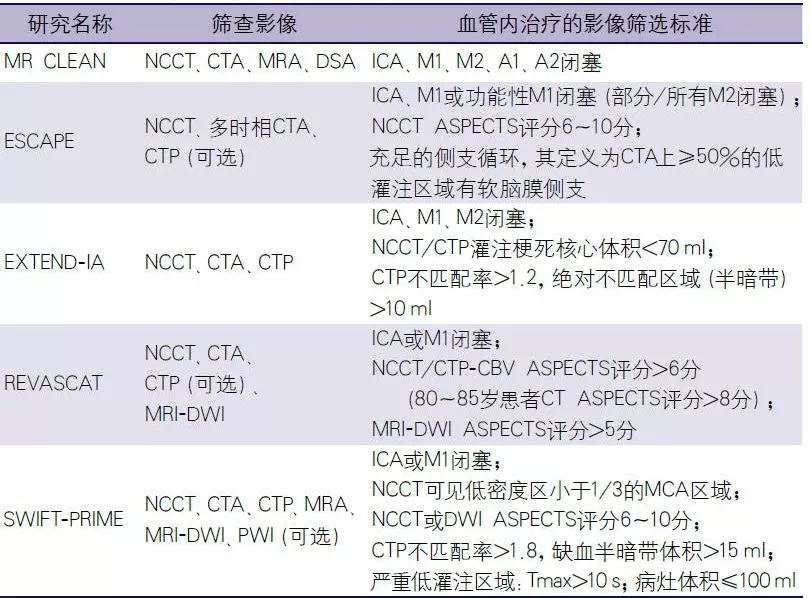

研究之所以取得阳性结果,除了选用了新一代取栓装置外,还应用了影像学技术对患者进行了严格的筛选,主要包括平扫计算机断层扫描(noncontrast computed tomography,NCCT),多模式计算机断层扫描(computed tomography,CT),如CT血管成像(CT angiography,CTA)、CT灌注成像(CT perfusion,CTP),多模式磁共振成像(magnetic resonance imaging,MRI),如弥散加权成像(diffusion weighted image,DWI)、灌注加权成像(perfusion weighted image,IPWI)、磁共振血管成像(magnetic resonance angiography,MRA)。这些影像学技术可以排除出血性病变、识别闭塞血管部位以及通过直接或间接征象评估梗死核心灶、缺血半暗带及侧支循环,以此识别通过取栓可能获得良好预后的患者(表1)[7]。

表1. 5项急性缺血性卒中血管内治疗试验的影像评估

注:MR CLEAN:血管内治疗急性缺血性卒中的多中心随机临床试验;ESCAPE:前循环近端闭塞小梗死灶血管内治疗试验;EXTEND-IA:应用动脉内治疗延长急性缺血性卒中溶栓时间研究;REVASCAT:对8h内前循环卒中应用Solitaire取栓vs最佳药物治疗实现血管内再通比较;SWIFT-PRIME:Solitaire支架取栓治疗急性缺血性卒中试验;Tmax:残留功能区实现灌注的最大时间;NCCT:平扫计算机断层扫描;CTA:计算机断层扫描血管成像;CTP:计算机断层扫描灌注;CBV:脑血容量;MRA:磁共振血管成像;DWI:磁共振弥散加权成像;PWI:磁共振灌注加权成像;DSA:数字减影血管造影;ASPECTS:Alberta卒中项目早期计算机断层扫描评分;ICA:颈内动脉;MCA:大脑中动脉;M1、M2:大脑中动脉的M1段、M2段;A1、A2:大脑前动脉的A1段、A2段